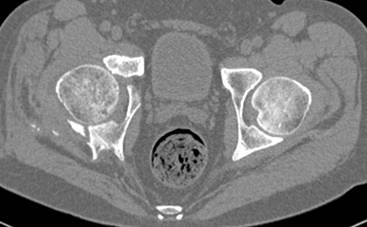

высылаю дополнительно сканы.

Судя по представленным реконструкциям (не очень хорошего качества - много наводок)

По отдельным срезам и тем более по реконструкции трудно судить о сращении крыла и задней колонны с осевым скелетом.

В большинстве случаев при двухколонных переломах

в итоге получается прочный бублик с дыркой. При эндопротезировании в дырку помещается головка, а чашка должна неплохо заклиниться в бублике.

Главное, чтобы бублик не был разорван, что не очень понятно на представленных снимках.

Поэтому хотелось бы дообследовать больного (разумеется включив стандартные проеции judet,и срезы показывающие сращение)

Хорошо бы на рентгенограммы взглянуть и побольше срезов по своду. С каким отломком головка контактирует и как ее состояние.

Из того минимума, что представлено, мне кажется, мы имеем дело с двухколонным переломом вертлужной впадины. Обычно медиальный (центральный) "вывих" головки встречаются в сложных двухколонных переломах со смещением.